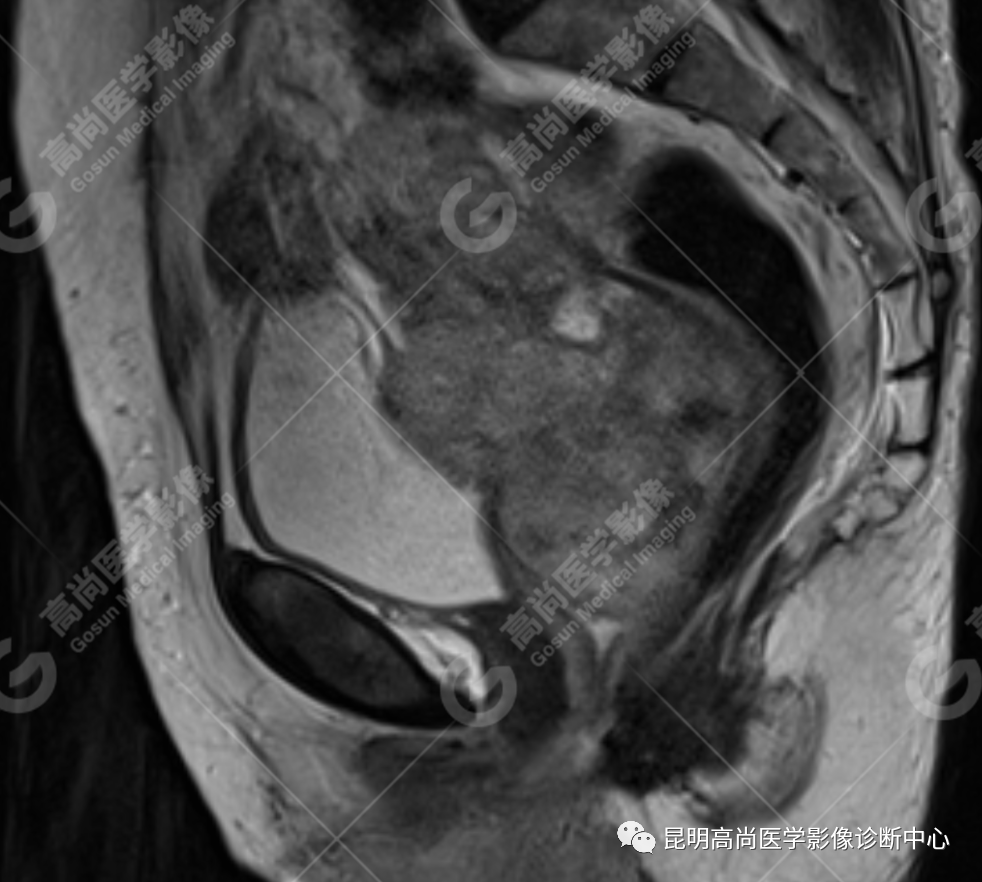

影像诊断

子宫、附件未见显示;下腹部及盆腔内巨大占位,考虑恶性肿瘤,肉瘤可能,阴道及肛管受侵,建议活检。

MRI 表现

不规则菜花状或息肉状肿物,子宫内膜正常 T2WI 清晰连续的高信号消失,取而代之是中高、高信号,不均匀混杂信号,信号强度低于内膜正常信号强度,T1WI 上内膜信号增高,子宫肌层明显变薄,未受侵者肌层信号均匀,因肿物组织来源不同,病变信号复杂,以 T2WI 表现为等高混杂信号为主。因病灶较大,可合并囊变坏死及肿瘤出血。

肌层到肿块内的血管流空信号,可提示肿瘤内有血供丰富的肉瘤成分,血管流空信号在子宫内膜癌中未见报道,但在子宫平滑肌瘤、平滑肌肉瘤中可见。